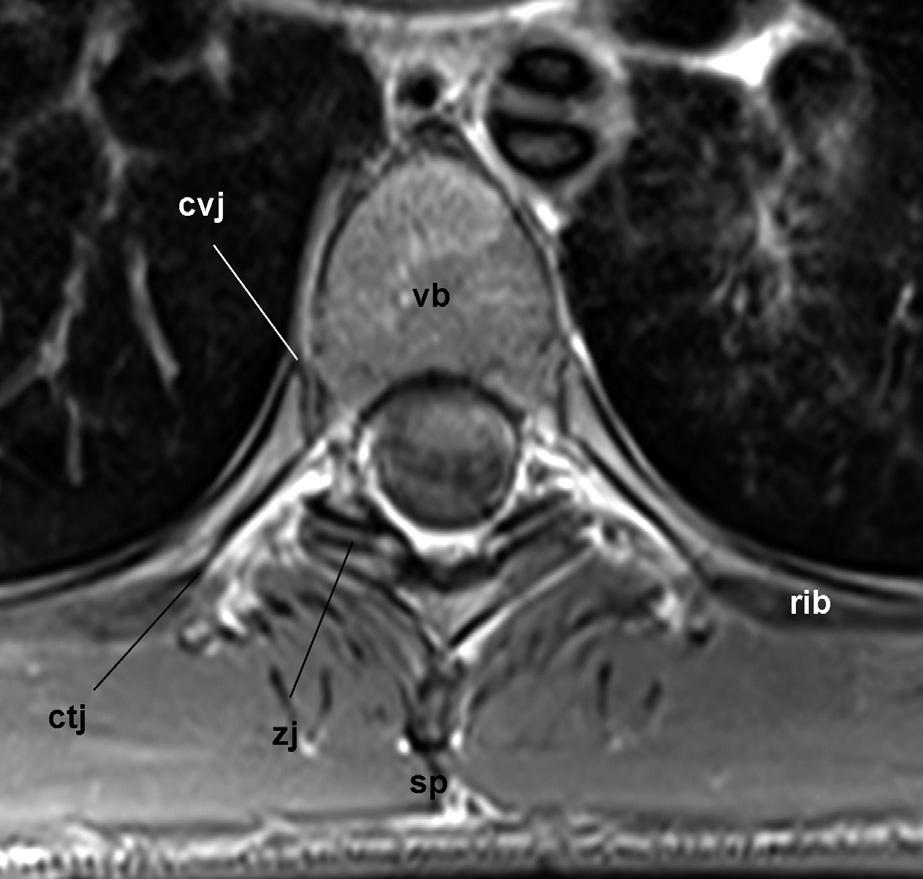

Likecervicalandlumbarvertebrae,thethoracicvertebraehavevertebralbodiesthatareconnectedbyintervertebraldiscsandlongitudinalligaments,andposterior elementsthatareconnectedbyzygapophysialjoints (Fig.32.14).Thedistinctionofthethoracicspineisthat itsuspendstheribs.Attypicalthoraciclevels,thehead oftheribarticulateswiththeintervertebraldiscand demifacetsontheedgesofthevertebraethatbindthat disc,andthearticulartubercleoftheribarticulateswith thetransverseprocessoftheupperofthetwovertebrae

Fig.32.15. Axialmagneticresonanceimageofatypicalthoracicspinalsegment.vb,vertebralbody;zj,zygapophysial joint;sp,spinousprocess;cvj,costovertebraljoint;ctj, costotransversejoint.(CourtesyofDr.TimMaus,Mayo Clinic,Rochester,MN.)

(Fig.32.15).ExceptionstothisarrangementoccuratT1 andatT11andT12,wheretheheadoftheribfullyarticulateswiththelike-numberedvertebrae.